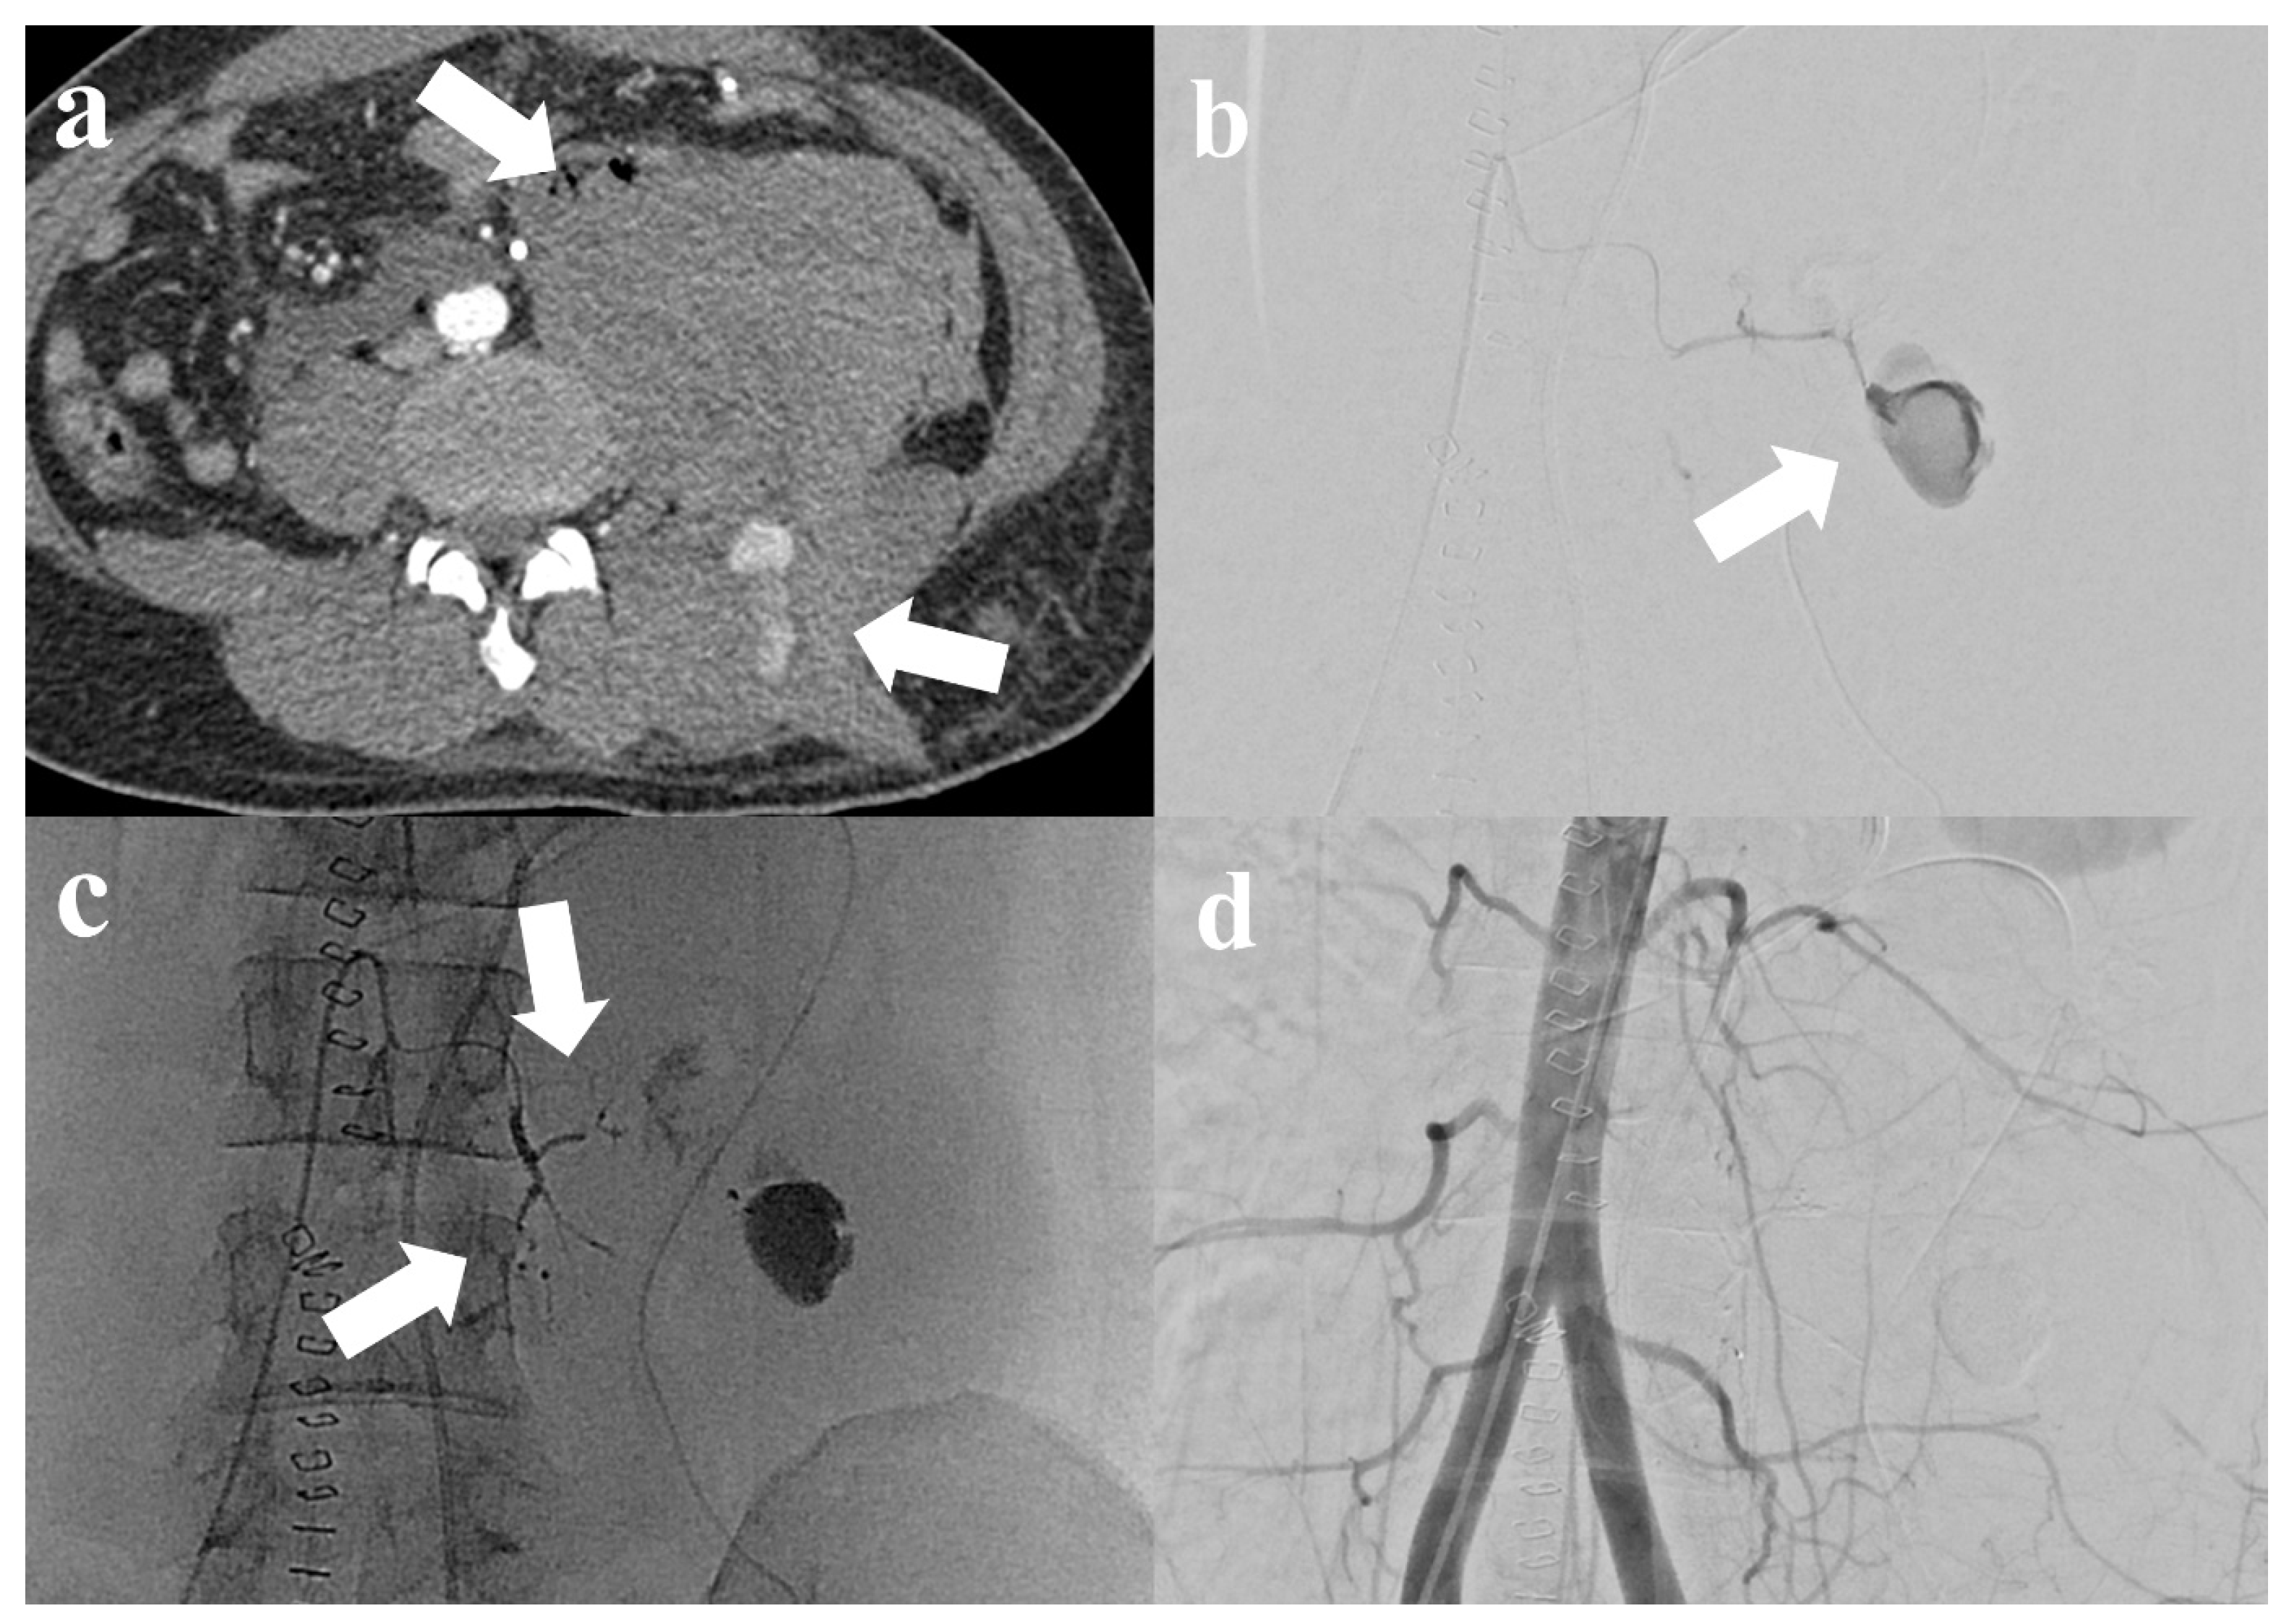

Figure 1.

A 32-year-old male patient with blunt trauma. (a) Computed tomography (CT) shows huge hematoma at left retroperitoneal space and paravertebral space with contrast media extravasation (arrow). (b) Selective left 3rd lumbar artery angiograms show huge pseudoaneurysm (arrow), consistent with CT. (c) Embolization was performed using n-butyl cyanoacrylate at the left 3rd lumbar artery (arrow). (d) After successful embolization, abdominal aortography shows the well-embolized left 3rd lumbar artery without definite residual active bleeding.